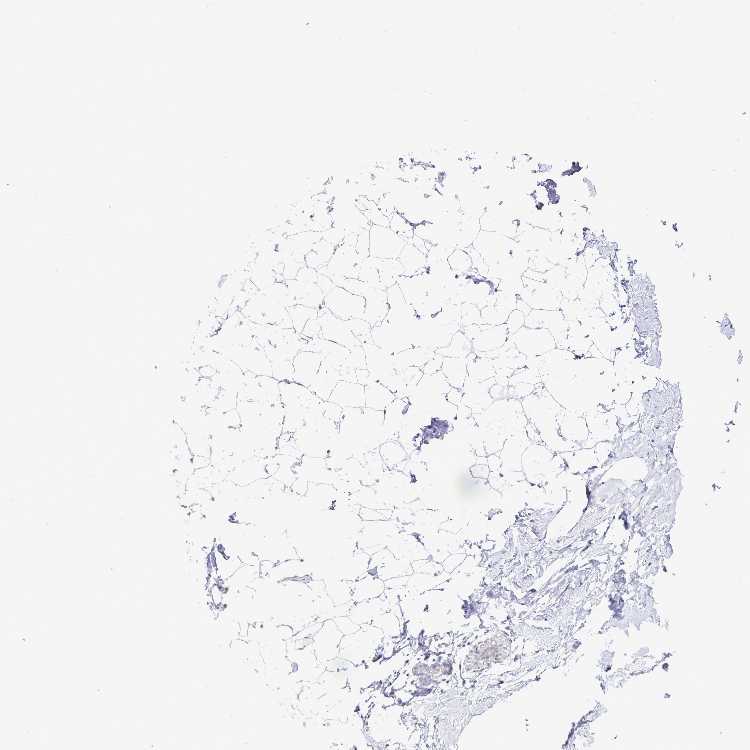

BREAST - Antibody stainingi

Antibody staining in the annotated cell types in the current human tissue is reported as not detected, low, medium, or high, based on conventional immunohistochemistry profiling in selected tissues. This score is based on the combination of the staining intensity and fraction of stained cells.

Each image is clickable and will lead to virtual microscopy that enables deeper exploration of all samples and also displays staining intensity scores, fraction scores and subcellular localization as well as patient and tissue information for each sample.

Antibody HPA055327

Adipocytes Not detected

Glandular cells Not detected

Myoepithelial cells Not detected